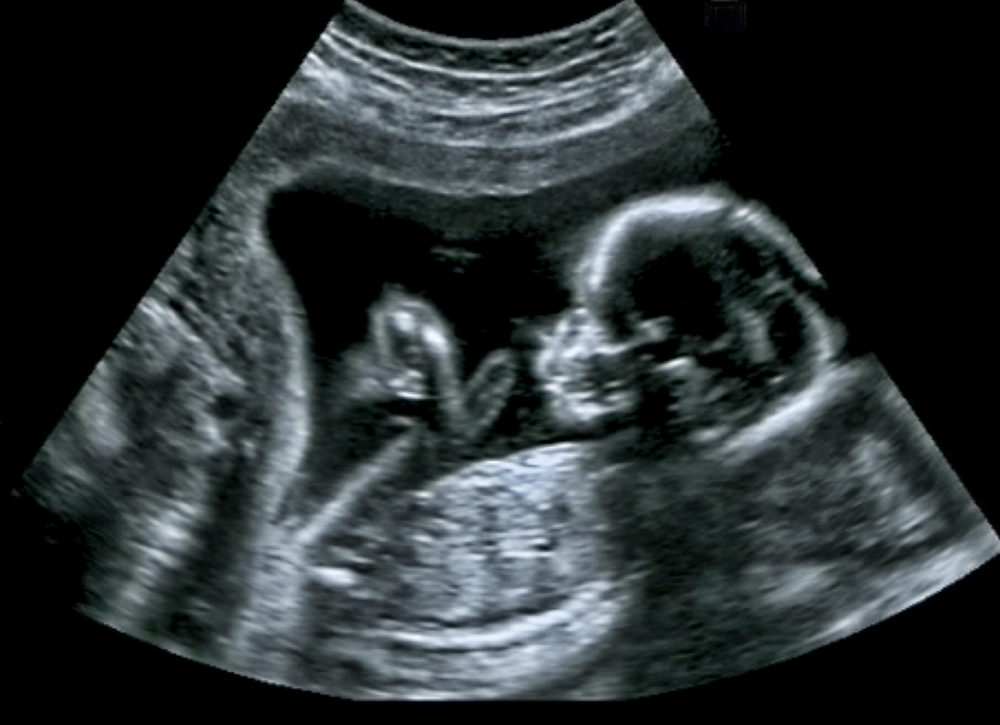

What to expect in the ultrasound at the 29th week

Like in the past week, this week too, your baby is mostly focusing on internal growth so very few external changes can be visible in the ultrasound. Here are some of the things you can see in the ultrasound on the 29th week.